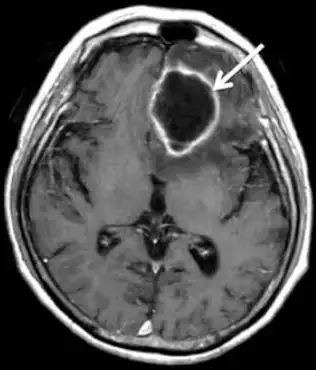

| MRI of brain revealed a mass in left frontal lobe that was ring-enhanced | |